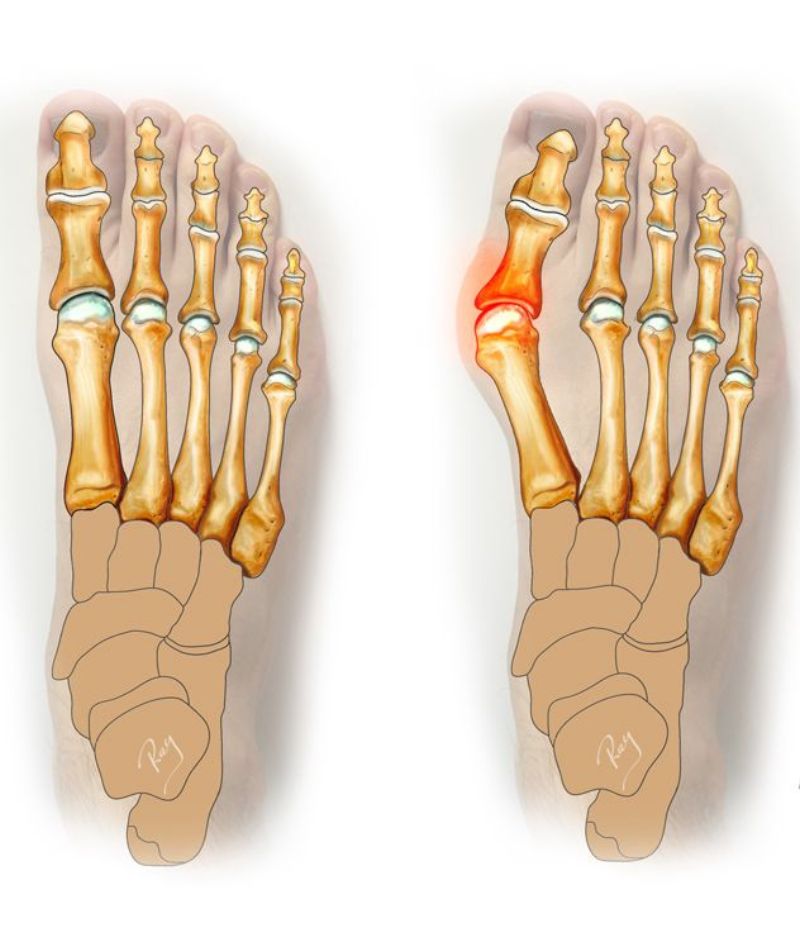

Typically thought of as a bump on the side of the toe’s. This may reflect changes in appearance of the alignment of the toe’s and also the anatomy. This happens overtime and has a genetic or hereditary component. It also is associated with patient of flat foot as well as people wearing tight shoes or pointed shoe’s. Symptoms felt by the patients range from pain, inflammation, swelling, redness and/or discomfort. Diagnosis is made by clinical and history taking and grading of severity over radiographs. Treatment mostly consists of conservative management which can be in the form of non- steroidal anti-inflammatory drugs, pads, spacers, exercises, shoe modifications and/or orthosis. When the severity is more surgical treatment is the only option. The goal of the surgery is not the cosmetic but the alignment of the toe’s.

- Genetics, inherited foot structure and biomechanics

- Flat feet or overpronation, placing extra stress on the big toe joint